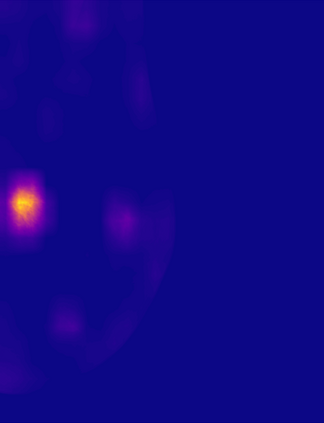

Breast cancer is the most widespread neoplasm among women and early detection of this disease is critical. Deep learning techniques have become of great interest to improve diagnostic performance. Nonetheless, discriminating between malignant and benign masses from whole mammograms remains challenging due to them being almost identical to an untrained eye and the region of interest (ROI) occupying a minuscule portion of the entire image. In this paper, we propose a framework, parameterized hypercomplex attention maps (PHAM), to overcome these problems. Specifically, we deploy an augmentation step based on computing attention maps. Then, the attention maps are used to condition the classification step by constructing a multi-dimensional input comprised of the original breast cancer image and the corresponding attention map. In this step, a parameterized hypercomplex neural network (PHNN) is employed to perform breast cancer classification. The framework offers two main advantages. First, attention maps provide critical information regarding the ROI and allow the neural model to concentrate on it. Second, the hypercomplex architecture has the ability to model local relations between input dimensions thanks to hypercomplex algebra rules, thus properly exploiting the information provided by the attention map. We demonstrate the efficacy of the proposed framework on both mammography images as well as histopathological ones, surpassing attention-based state-of-the-art networks and the real-valued counterpart of our method. The code of our work is available at https://github.com/elelo22/AttentionBCS.